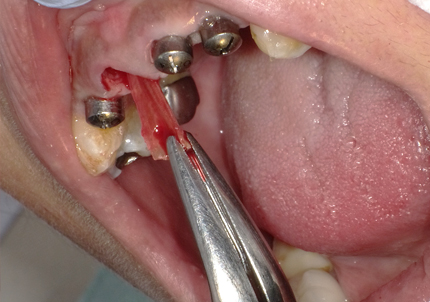

4.右上2番 S.S.T(ソケットシールドテクニック)

5.左上1番 S.S.T(ソケットシールドテクニック)

6.左上2番 S.S.T(ソケットシールドテクニック)

11.舌側歯牙片の抜歯